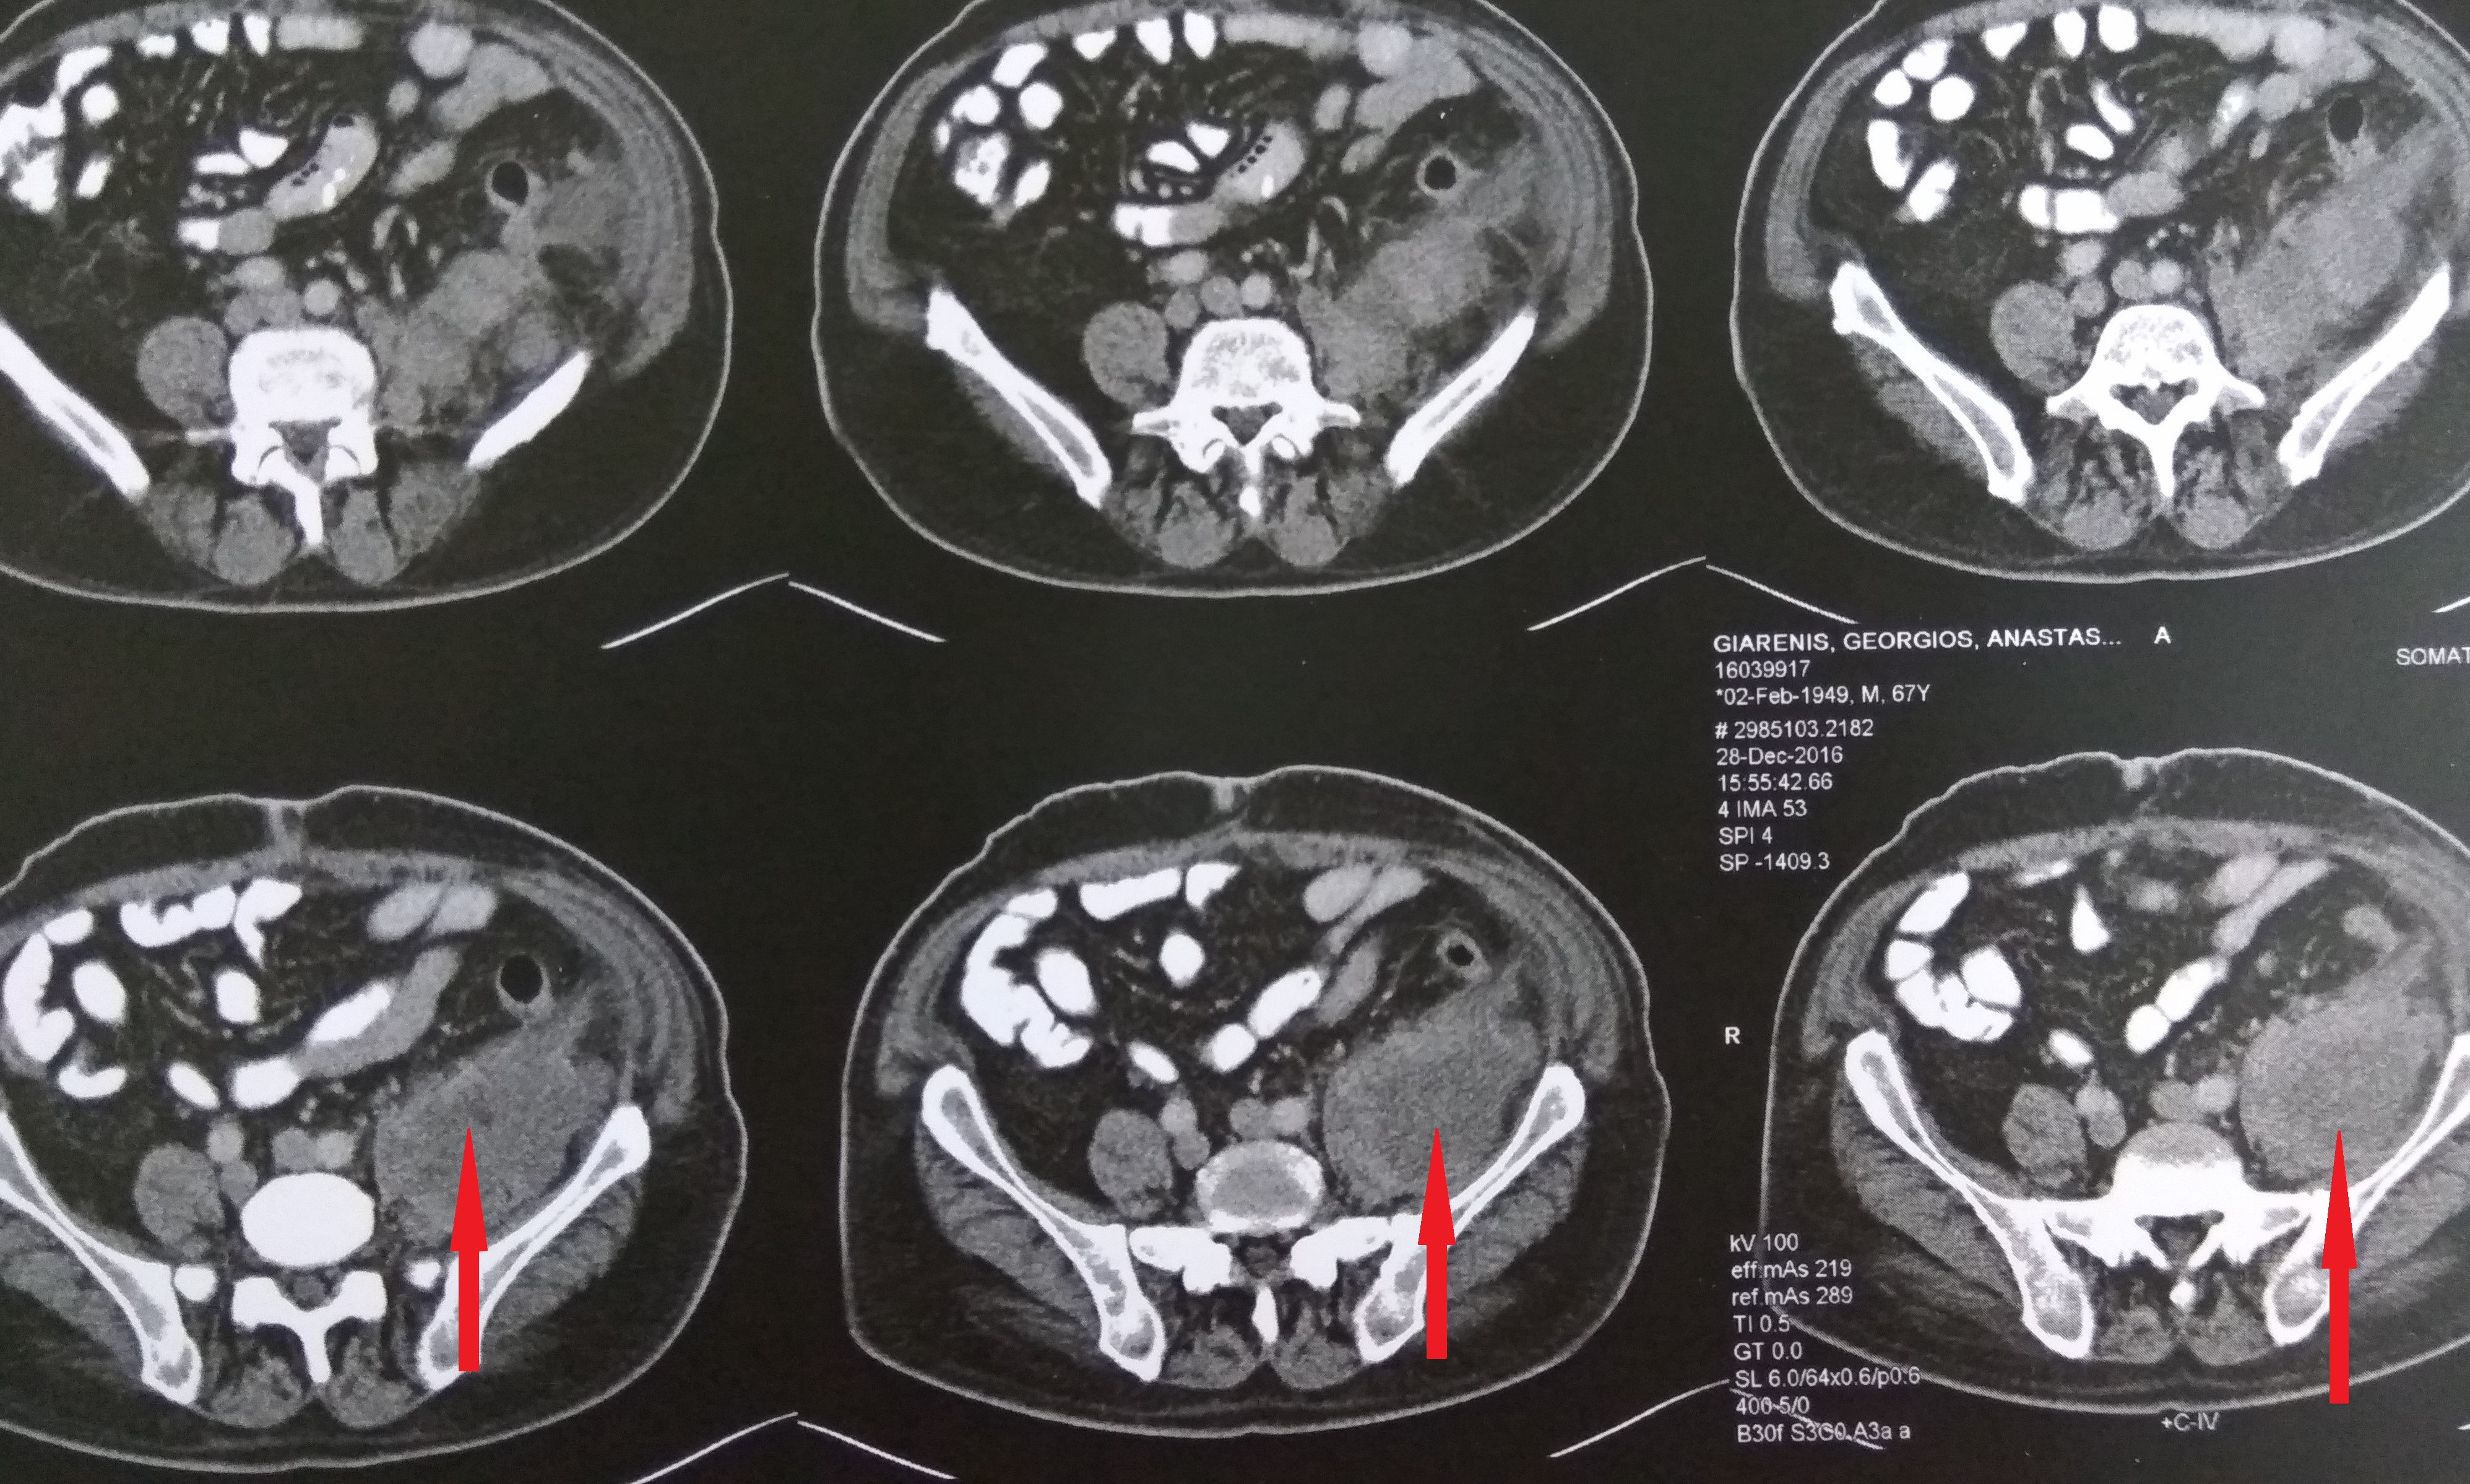

Αξονική τομογραφία κοιλίας. Φεβρουάριος 2017. Εμφανίζεται η υποτροπή του οπισθοπεριτοναϊκού αγγειοσαρκώματος (κόκκινα βέλη)